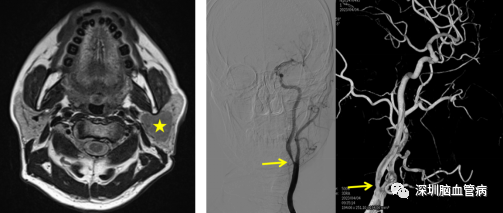

图1 左图:MRI提示“左侧腮腺实性肿物”(黄色星号)。右图:脑血管造影提示“左侧颈内动脉起始部重度狭窄”(黄色箭头)。

来自安徽的方先生,今年74岁,患有左侧腮腺肿瘤2年多,近期来到深圳市第二人民医院耳鼻喉科就诊,腮腺彩超检查提示“左侧腮腺实质性占位病变”,术前的颈部血管彩超发现左侧颈内动脉起始部重度狭窄,考虑到围手术期风险高,神经外科血管病区伍健明主任团队为方先生进行了全脑血管造影,评估结果显示“左侧颈内动脉起始部斑块形成,管腔重度狭窄”,需要手术干预。此种情况,通常采取分期手术,患者需要忍受两次手术的痛苦。神经外科与耳鼻喉科通过多学科协作,共同为方先生制定了手术方案,计划使用同一个切口,一次手术同时治疗颈动脉狭窄和腮腺肿瘤。